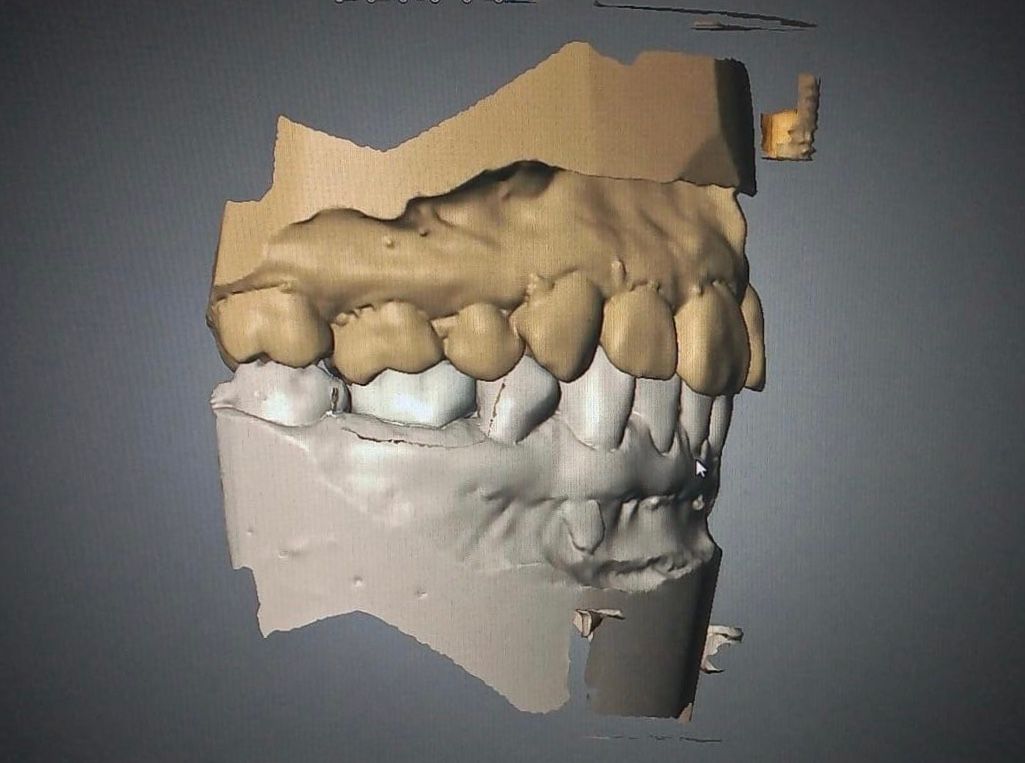

La especialidad en prótesis Bucal se enfoca en rehabilitar mediante prótesis unitarias, múltiples o totales la función masticatoria de nuestros pacientes brindándoles una mejor estética dental, confort, anatomía dental y función.

Contamos con tecnología de punta que nos facilitara el diagnostico y tratamiento de tu problema dental lo cual hará mas predecible el éxito a largo plazo.